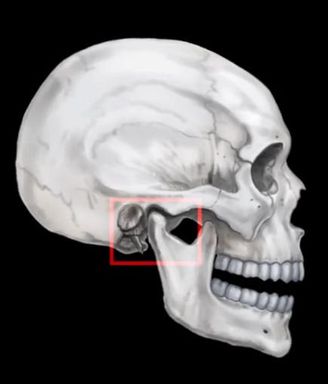

턱에서 소리가 난다면 턱관절 질환일 수 있습니다.

안녕하세요 목동안치과의 안상우 원장입니다. 최근에 들어서는 턱관절이 불편하다고 내원하시는 환자분들이 늘었습니다. 턱을 벌릴때 소리가 나거나 아예 턱이 안벌어지는 경우도 있고 어떤분은 통증에 시달리시는 분들도 있습니다. 턱관절의 경우 통증이 생기기 시작하면 정말 걷잡을 수 없이 신경이 쓰이고 괴로운데요. 턱관절 질환이 생기는 원인과 예방법 그리고 치료방법에 대해서 알아보겠습니다.우리의 턱뼈는 크게 두부분으로 이루어져 있는데요. 하악(아래턱)과 상악(윗턱)입니다. 이 하악과 상악이 서로 만나는 지점이 있는데 이 부분을 턱관절(Temporomandibular Joint;TMJ)이라고 부릅니다. 이 턱관절에는 아래턱의 과두(Condyle)가 윗턱의 관절와(Fossa)에 위치하고 있어서 마치 문의 경첩(Hinge)와 같이 위아래로 턱을 열었다 닫았다 하는 기능을 하고 있습니다.두 뼈가 마주하고 있기 때문에 뼈사이에는 어께나 무릎처럼 연골이 들어가 있는데 이 연골을 관절원판(Articular Disk)이라고 합니다.턱관절에 문제가 생기는 이유는 여러가지가 있을 수 있는데 주로 원인이 되는 것이 턱에 과도한 힘이 들어가는 현상 때문입니다. 치아가 닿은 상태에서 턱관절에 하악과두가 들어가고 교근이 작용을 하게 되면 힘이 가해지면서 턱관절에 힘이 들어가게 됩니다. 치아와 2개의 턱관절 이 3포인트가 접촉이 되어야만 턱관절에 힘이 들어가게 되요.결과적으로 치아에 힘이 들어가지 않는다면 턱괴기와 같은 행동을 하지 않는다면 턱관절에도 힘이 들어가지 않습니다.턱관절을 치료하는 첫번째 방법은 결과적으로 이 턱관절에 들어가는 힘을 줄이는 것 입니다. 턱을 괴거나 하는 것이 아닌 이상 치아가 닿았을 경우에만 턱관절에 힘이 들어가거든요. 따라서 치아가 닿는 시간을 최소한으로 하고 치아가 닿는 순간에도 평소보다 1/2의 힘이 들어가게 행동조절을 하게 되면 턱관절에 들어가는 힘을 줄일 수 있습니다.대부분의 턱관절질환을 가지고 있는 분들은 이 힘을 조절하는데 어려움을 가지고 있는 경우가 많아요.턱관절을 치료하는 첫번째 방법은 결과적으로 이 턱관절에 들어가는 힘을 줄이는 것 입니다. 턱을 괴거나 하는 것이 아닌 이상 치아가 닿았을 경우에만 턱관절에 힘이 들어가거든요. 따라서 치아가 닿는 시간을 최소한으로 하고 치아가 닿는 순간에도 평소보다 1/2의 힘이 들어가게 행동조절을 하게 되면 턱관절에 들어가는 힘을 줄일 수 있습니다.이렇게 행동 조절을 했음에도 불구하고 통증이 지속되는 경우에는 깨어 있을때가 아닌 무의식중, 예를 들면 수면 중이나 이상 악기능에 의해서 턱관절에 무리한 힘이 들어가는 현상이 있을수 있어요.이런 습관은 의식적으로 줄일 수 없기 때분에 이런경우에는 턱관절치료의 두번째 단계인 약물 치료를 하게 됩니다. 1주일 정도 근육이완제를 복용하거나 턱근육에 보톡스를 맞음으로써 턱관절에 가는 하중을 줄이게 되요. 물론 이단계에서도 행동교정을 같이 해야 합니다.대부분의 환자분들이 두번째 치료에서 호전되는 경우가 많습니다.약물치료를 했음에도 불구하고 통증이 지속되거나 행동조절을 하기 힘든 경우에는 마지막으로 턱관절치료의 3단계인 스플린트라고 하는 교합안정장치(Splint)를 제작하게 됩니다. 이 교합안정장치는 자는 도중에 장착을 함으로써 치아가 과도하게 물리는 것을 방지해서 턱관절에 들어가는 힘을 줄이는 장치입니다. 턱관절 질환의 경우 어느정도 진행이 되면 원상복구 하기가 힘들어 집니다. 턱관절질환의 치료방법은 질환이 진행된 상태에서 더 이상 악화 되는것을 방지하는 것이라고 볼 수 있어요. 따라서 턱관절 질환이 있거나 초기 증상이 있다면 빠른시간에 행동교정이나 약물치료등으로 더이상 진행이 되지 않도록 해야 합니다 .평소에 이를 꽉물거나 단단한 음식을 좋아하는 습관이 있지는 않은지 잘 살펴보시고 그런 습관을 줄이는게 턱관절 질환을 예방하는 방법입니다.